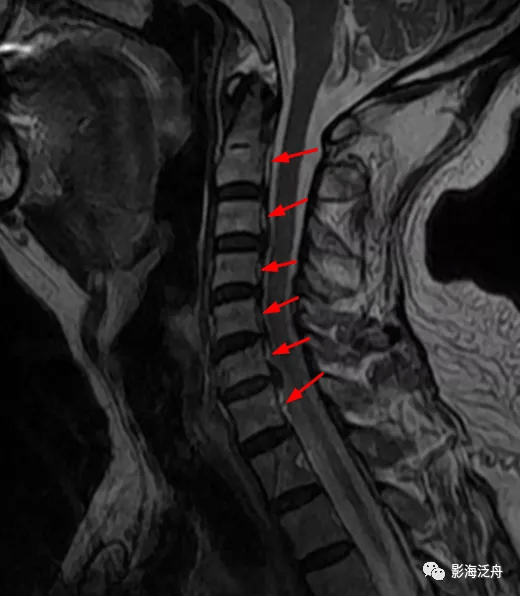

典型病例颈椎后纵韧带钙化mr